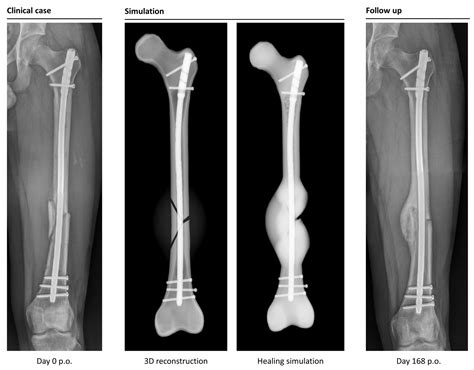

• Surgical Technique: Most femur fractures are treated with an intramedullary nail (a metal rod inserted into the bone). The precision of the hardware placement is vital to early mobilization.

• Soft Callus Formation: Within two weeks, the body starts replacing the clot with cartilage, bridging the gap between the bone fragments.

• Hard Callus Formation: Over the next few months, this cartilage is converted into hard, bony tissue, providing structural stability.

• Remodeling: This is the final, longest stage. The bone is continuously reshaped and strengthened by the body, which can take up to two years to fully complete.